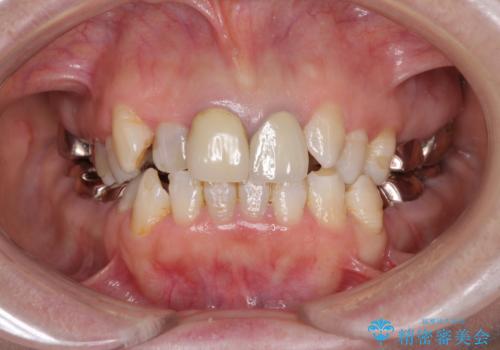

- 全顎的な歯列不正と、銀歯だらけの奥歯を気にして来院された患者様です。

奥歯の銀歯は、セラミッククラウンを装着するには歯の高さが不十分であり、そのままでは矯正治療を行うことが困難であるため、歯冠長延長術を行うこととしました。

また、根管治療の必要な歯がいくつかあるため、歯周外科治療の治癒期間を利用して根管治療を行い、その後インビザラインにて矯正治療を行うこととしました。